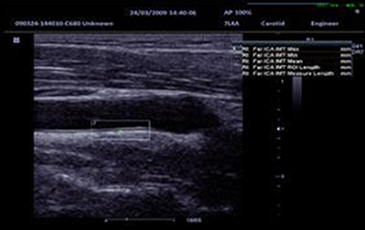

IMT (определение толщины комплекса интима-медиа)

Автоматическое измерение толщины передней и задней стенок, предоставляющее точную информацию о состоянии сонной артерии.